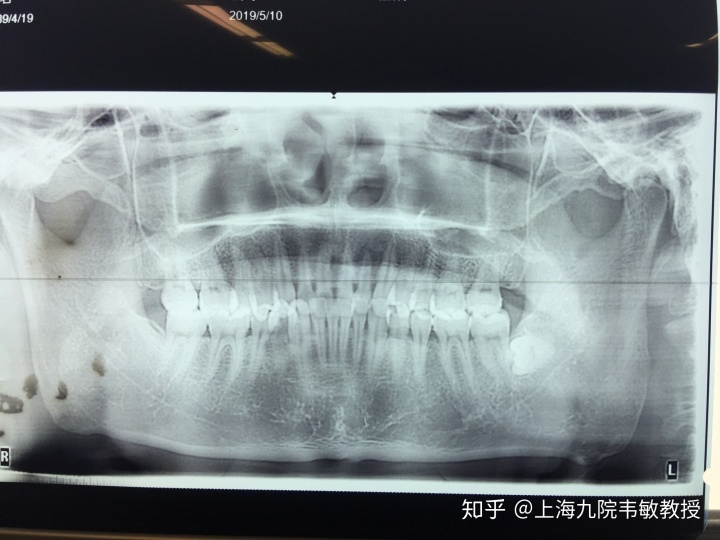

为了改变自己,小张在多方打听下终于找到了这方面的专家韦敏教授。韦敏教授是面部整形的首选专家,通过面诊设计,确定了手术方案为:下颌角最大化截骨术+咬肌去除术。

对于这种骨骼与咬肌共同肥厚的症状,韦敏教授认为,如果单纯截取一项,都远达不到可观的效果。其中咬肌去除量需要准确掌握,因为下颌角截骨缩窄后,部分咬肌开始寻找新的附着点而相应缩小,而此时我们要去除的是仍然突出的部分咬肌量,所以有经验的颅颌面医生需在手术前便要很精确的测量出咬肌量。

韦敏教授此次顺利截除小张两侧超大下颌角,且每侧截取长度超过7.5cm,角度内板切除2.6cm。此外还去除了小张3ml厚的咬肌,将脸型最大化缩窄超过3cm。